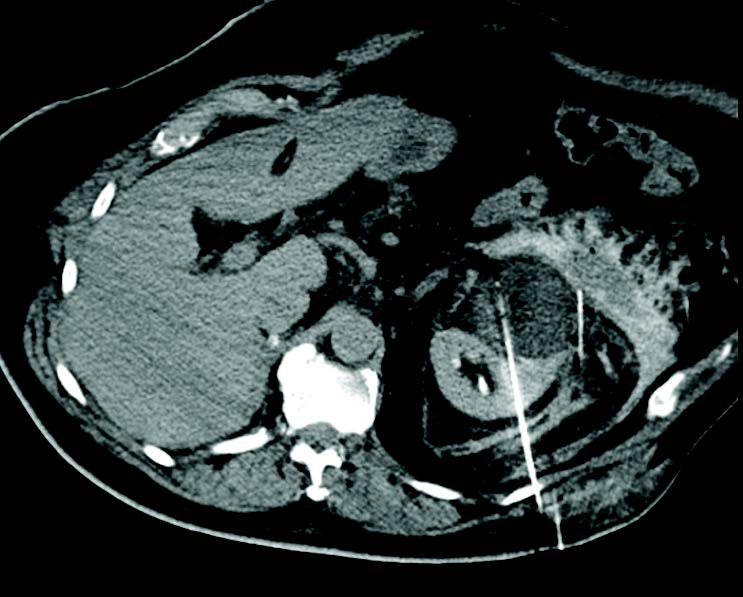

Cryoablation of 7cm left renal tumor Cryoablation of 7cm left renal tumor

Cryoablation of 7 cm Renal Tumor after Previous Contralateral Nephrectomy

A 78-year-old man presented with right kidney multifocal RCC with vein invasion and concurrent 7 cm left anterior conventional clear cell RCC. The right tumor was treated with nephrectomy and the left tumor was treated with cryoablation 3 months after the nephrectomy. Hydrodissection was used to protect adjacent structures and 7 IceRod™ 1.5 PLUS needles were used to treat. There were no reported adverse events and early follow-up imaging of the left kidney confirmed adequate ablation.

Alex King, MD I University Hospital Southampton I Southampton, UK